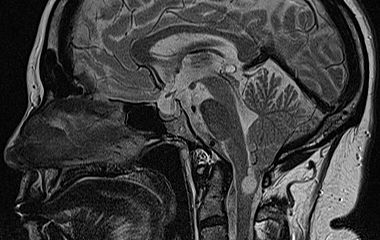

Der Bereich Hydrozephalus, Chiari-Malformation und Tethered-Cord-Syndrom umfasst die Diagnostik und Behandlung komplexer Erkrankungen des Liquorsystems sowie des Gehirns und Rückenmarks. Wir behandeln angeborene und erworbene Formen des Hydrozephalus, einschließlich des Normaldruckhydrozephalus, der sich häufig durch Gangstörungen, kognitive Veränderungen und Blasenfunktionsstörungen äußert. Ein weiterer Schwerpunkt ist die Chiari-Malformation, bei der es zu einer Verlagerung von Kleinhirnanteilen in den Spinalkanal kommen kann und die vielfältige neurologische Symptome verursachen kann. Das Tethered-Cord-Syndrom beschreibt eine krankhafte Fixierung des Rückenmarks, die sowohl in klassischer als auch in okkulter Form auftreten und zu Schmerzen, neurologischen Defiziten oder Funktionsstörungen führen kann. Ziel unserer Behandlung ist es, neuralen Strukturen zu entlasten, eine weitere Schädigung zu verhindern und die Lebensqualität der Patientinnen und Patienten zu verbessern. Grundlage hierfür sind eine präzise Diagnostik, individuell abgestimmte Therapiekonzepte und eine umfassende, verständliche Aufklärung.

Arnold-Chiari Malformation

Bei Hydrozephalus bieten wir verschiedene Formen der Liquorableitung an, darunter den Liquorshunt und den ventrikuloperitonealen Shunt (VP-Shunt), individuell angepasst an die jeweilige Erkrankung. Als alternative, shuntunabhängige Therapie führen wir die endoskopische Drittventrikulozisternostomie (ETV) durch, sofern die anatomischen Voraussetzungen gegeben sind. Patientinnen und Patienten mit Arnold-Chiari-Malformation behandeln wir durch eine gezielte mikrochirurgische Dekompression, um den Liquorfluss zu verbessern und neurologische Symptome zu lindern. Beim Tethered-Cord-Syndrom, einschließlich okkulter Formen, setzen wir auf ein minimalinvasives Detethering zur schonenden Entlastung des Rückenmarks.